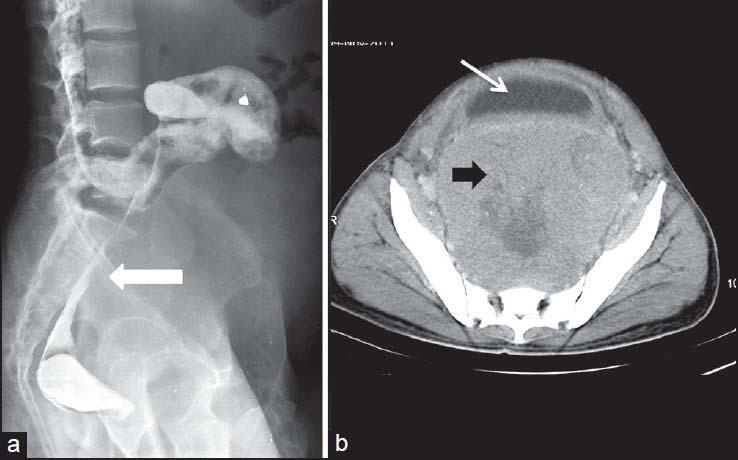

| Figure 5:Rectal gastrointestinal stromal tumors in a 49-year-old male — (a) barium enema spot image lateral view showing extrinsic impression on rectal wall (arrowhead) (b) axial contrast-enhanced computed tomography image showing heterogenously enhancing necrotic mass in pelvis (black arrowhead) displacing the urinary bladder (arrow) anteriorly

| Figure 5:Rectal gastrointestinal stromal tumors in a 49-year-old male — (a) barium enema spot image lateral view showing extrinsic impression on rectal wall (arrowhead) (b) axial contrast-enhanced computed tomography image showing heterogenously enhancing necrotic mass in pelvis (black arrowhead) displacing the urinary bladder (arrow) anteriorly